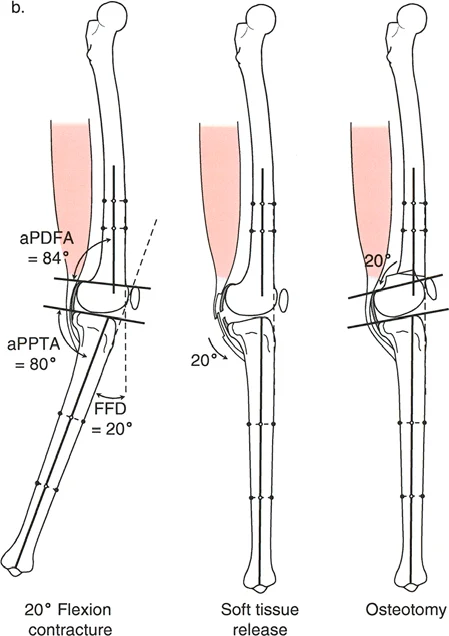

تصحيح تحدد حركة الركبة (Flexion Deformity - FFD)

تحدُّد حركة الركبة هو عدم القدرة على مد الركبة بالكامل. يمكن أن يكون سببه عظميًا أو ناتجًا عن تقلص في الأنسجة الرخوة.

- التشخيص الدقيق: يجب تحديد ما إذا كان تحدد الحركة ناتجًا عن تشوه عظمي (تقوس أمامي في الفخذ أو الساق) أو تقلص في الأنسجة الرخوة (الأوتار الخلفية، محفظة المفصل).

- تحرير الأنسجة الرخوة (Soft Tissue Release):

- إذا كان السبب هو تقلص الأنسجة الرخوة، فقد يتم إجراء إطالة للأوتار أو تحرير لمحفظة المفصل.

- التصحيح التدريجي: في حالات تحدد الحركة الشديدة أو المعقدة، قد يكون التصحيح التدريجي باستخدام التثبيت الخارجي هو الخيار الأكثر أمانًا.